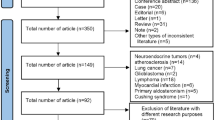

Abstract

We provide updated guidance and standards for the indication, acquisition, and interpretation of [18F]FDG PET/CT for plasma cell disorders. Procedures and characteristics are reported and different scenarios for the clinical use of [18F]FDG PET/CT are discussed. This document provides clinicians and technicians with the best available evidence to support the implementation of [18F]FDG PET/CT imaging in routine practice and future research.